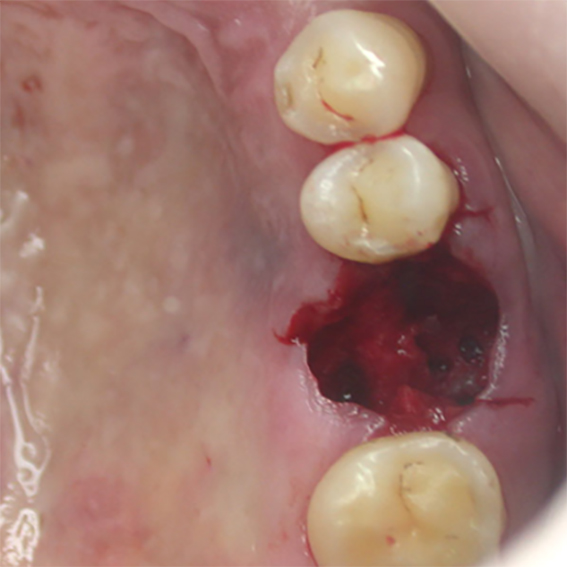

Pure titanium membrane of ultra-thin thickness of about 10 microns (0.01mm). Totally inert, biocompatible and non-biological thus removing the fear of disease transmission from collagen of bovine source. It allows ease of handling and adaptation over the operative site. Because of its mouldability, it does not require pin or screw fixation, thus avoiding the risks of pin or screw swallowing or aspiration. Excellent clinical performance in guided tissue regeneration. Resistance to infection after exposure. Primary wound closure is not necessary. No tissue reaction or wound infection.